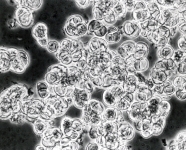

| Species Name: | Alternaria caespitosa |

| Taxonomy: | FUNGI Ascomycota, Dothideomycetes, Pleosporales, Pleosporaceae |

| Substrate: | chromomycosis-like skin infection, forearm, male 54 yr | Location: | SPAIN Zaragosa (GEO: 41.646,-0.888) |